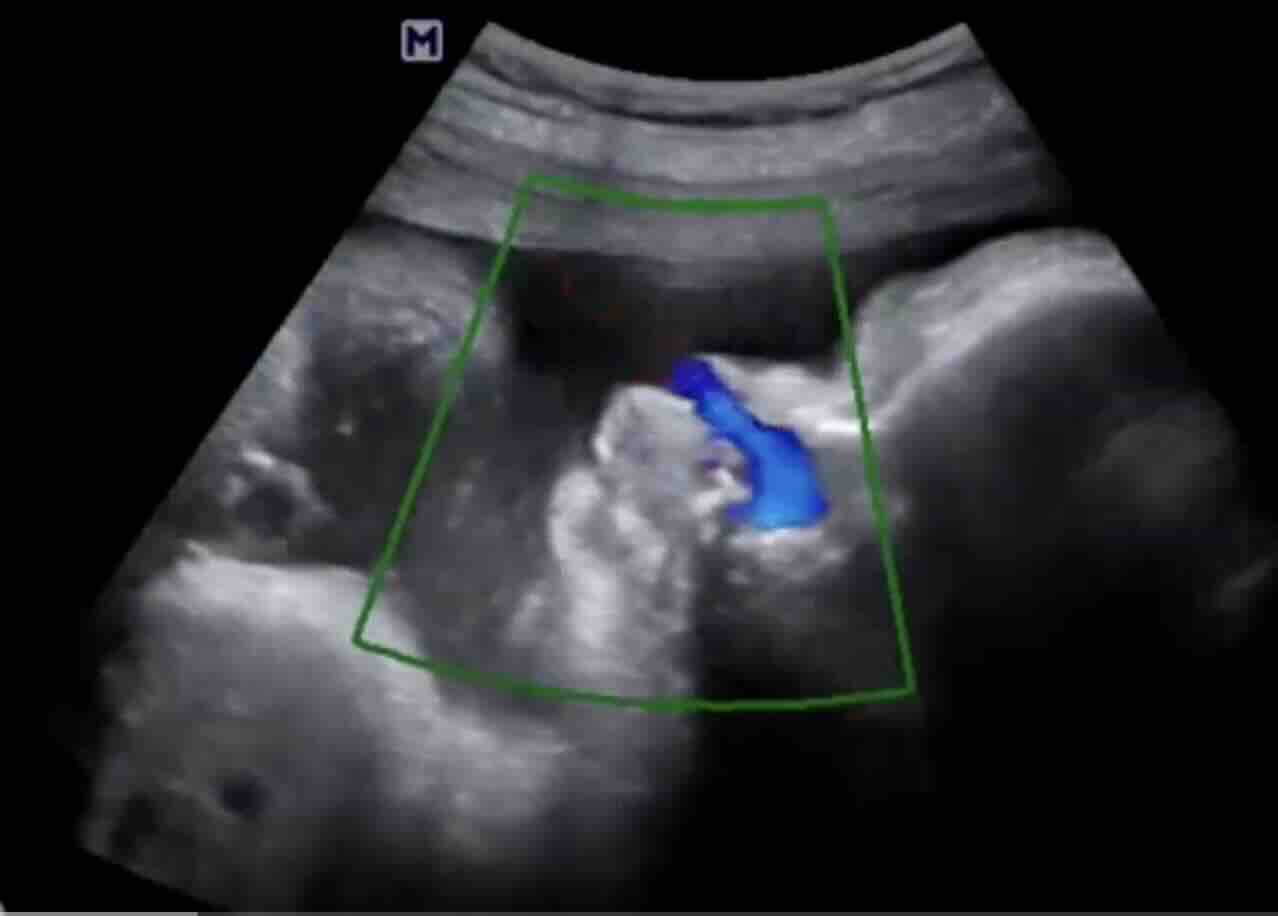

Kolposkopi:

- Anormal Pap smear veya pozitif yüksek riskli HPV testi sonucunda yapılan daha detaylı bir rahim ağzı incelemesidir.

- Kolposkop adı verilen özel bir mikroskop/büyüteç kullanılarak rahim ağzı, vajina ve vulva büyütülerek incelenir.

- İşlem sırasında rahim ağzına bazı özel solüsyonlar uygulanır:

- Asetik Asit (%3-5): Anormal hücrelerin bulunduğu alanların beyazlaşmasına (asetobeyaz epitel) neden olur. Bu alanlar biyopsi için potansiyel hedeflerdir.

- Lugol İyot Çözeltisi (Schiller Testi): Normal skuamöz epitel hücreleri glikojen içerdiği için iyotu tutarak kahverengiye boyanır. Anormal hücreler (CIN, kanser) veya glandüler hücreler glikojen içermediği için iyotu tutmaz ve sarı renkte kalır (iyot-negatif alanlar).

- Kolposkopi sırasında şüpheli görülen alanlardan biyopsi alınır.